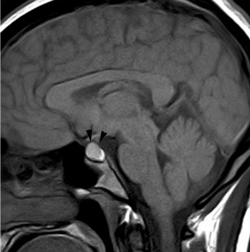

Figura 3A. Corte sagital, secuencia T1w. Glándula pituitaria en un recién nacido, muestra hiperseñal homogénea normal a esta edad.

Figura 3B. Corte sagital, secuencia T1w. Glándula pituitaria en lactante de 2 meses, muestra disminución de la hiperseñal de la adenohipófisis.

Figura 4A. Corte sagital, secuencia T1w. Glándula pituitaria normal en adulto joven (27 años), muestra foco posterior de hiperseñal de la neurohipófisis (punta de flecha); la señal de la adenohipófisis es similar a la de la protuberancia.

Figura 4B. Corte sagital, secuencia T2w.en el mismo paciente, la glándula pituitaria, muestra la neurohipófisis con leve hiperseñal (punta de flecha); la señal de la adenohipófisis es también similar a la protuberancia en esta secuencia.

Figura 4C. Corte sagital, secuencia T1w post inyección de Gadolinio. La glándula pituitaria, muestra refuerzo normal incluyendo el tallo pituitario; en el cerebro solo se refuerzan las estructuras vasculares.

Figura 5. Corte sagital, secuencia T1w. Examen realizado dos días postparto; muestra la pituitaria levemente mas intensa que la protuberancia, con un borde superior convexo (puntas de flecha), que ocupa la porción central inferior de la cisterna supraselar, lo que corresponde a hallazgos normales en esta condición.